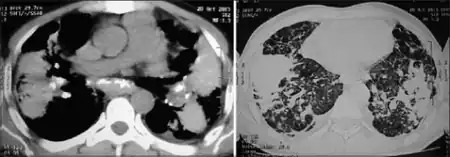

| Coalescence of nodules, lung parenchyma became fibrotic with appearance of bilateral conglomerated mass lesion, this confluent and consolidated shadow is indicative of progressive massive fibrosis | |

Progressive massive fibrosis (or Complicated pneumoconiosis[1]), characterized by the development of large conglomerate masses of dense fibrosis (usually in the upper lung zones), can complicate silicosis[2] and coal worker's pneumoconiosis.[3] Conglomerate masses may also occur in other pneumoconioses, such as talcosis,[4] berylliosis (CBD),[4] kaolin pneumoconiosis,[5] and pneumoconiosis from carbon compounds,[5] such as carbon black, graphite, and oil shale. Conglomerate masses can also develop in sarcoidosis,[6] but usually near the hilae and with surrounding paracicatricial emphysema.

According to the International Labour Office (ILO), PMF requires the presence of large opacity exceeding 1 cm (by x-ray). By pathology standards, the lesion in histologic section must exceed 2 cm to meet the definition of PMF.[7] In PMF, lesions most commonly occupy the upper lung zone, and are usually bilateral. The development of PMF is usually associated with a restrictive ventilatory defect on pulmonary function testing. PMF can be mistaken for bronchogenic carcinoma and vice versa. PMF lesions tend to grow very slowly, so any rapid changes in size, or development of cavitation, should prompt a search for either alternative cause or secondary disease.